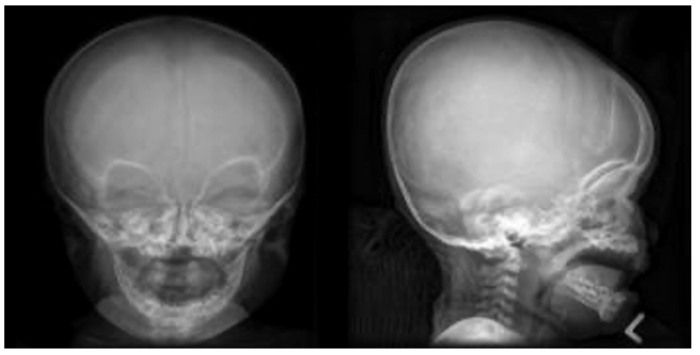

- They present with a large head size (macrocephaly), prominent forehead bossing, and a mid-face hypoplasia manifesting as a flattened nasal bridge and crowded, misaligned teeth (Figure 2). The pelvis is uniquely described to be champagne glass-shaped. This radiological appearance is characterized by flattened iliac blades, horizontal acetabulum, and narrowed sacroiliac notches.

Figure 2. Relatively large cranial vault with small skull base, prominent forehead with a depressed nasal bridge. Gaillard F, Walizai T, Ranchod A, et al. Achondroplasia. Reference article, Radiopaedia.org. Accessed on 24 Sep 2025. Link